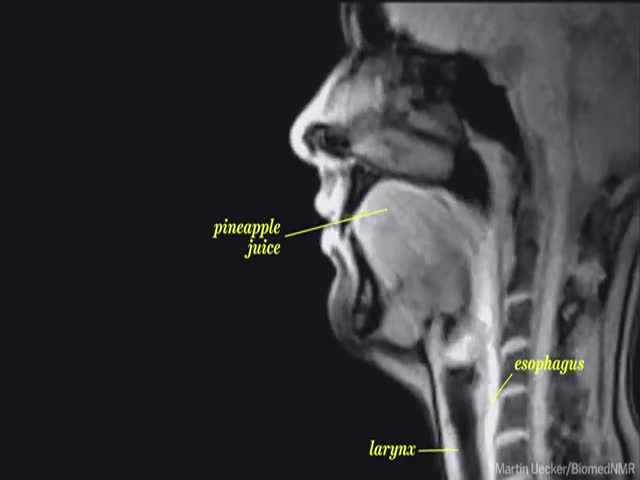

What Life Looks like Through an MRI Machine ?

See what eating, taking, playing music, gestating, having sex... looks like through an MRI machine.

NSFW because of the 'sex' part